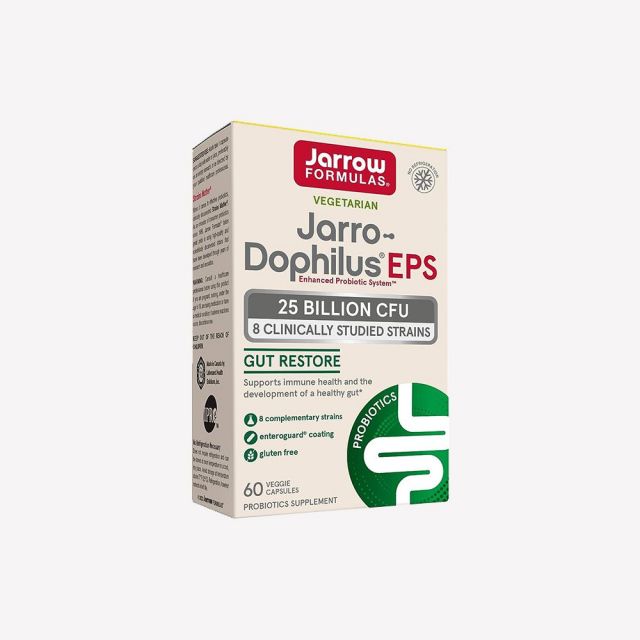

商品介绍

Jarro-Dophilus EPS® 臨床研究菌株

B. longum BB536、L. rhamnosus R0011 和 L. helveticus R0052 這些菌株經過充分表徵,並已證明能通過多種機制與腸道及其內部微生物生態系統互動。這些菌株在臨床研究中顯示能改善腸道微生物群的特性,促進腸道健康並支持免疫反應。

EnteroGuard® 確保益生菌能在小腸中最大限度地存活。

產品特點:

- Jarro-Dophilus EPS 每顆膠囊在消費時含有 25 億個活菌細胞,符合建議的儲存條件並在最佳使用前日期內。